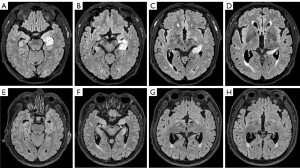

Correlation analysis between imaging changes in antibody-mediated AE and CSF/serum antibody titers, disease severity, treatment response, and prognostic score

Correlation analysis

Twenty-eight out of 45 cases exhibited abnormalities on brain MRI. Correlation analysis was then performed to assess the relationship between the severity of disease, CSF/serum antibody titers, response to treatment and prognostic score with the presence or absence of lesions on brain MRI. The results showed no significant correlation between antibody titers, disease severity, treatment response, prognostic score, and the presence or absence of lesions on brain MRI.

Further correlation analysis was conducted between the quantitative values of T1, T2, T2 FLAIR, and ADC within the ROI and the CSF and serum antibody titers, disease severity, treatment response, and prognostic score. A total of 41 cases were included in this quantitative analysis, as imaging data for the remaining four cases were unavailable. The results (Table S4) indicated that the ADC values within the ROI positively correlated with disease severity (r=0.6891, P<0.0001) and prognostic score (r=0.8102, P<0.0001) (Figure 8A,8B). However, there was no correlation between ADC values and treatment response (P>0.05). Additionally, the other quantitative values showed no correlation with CSF and serum antibody titers, disease severity, treatment response, or prognostic score (P>0.05).

Furthermore, based on the Dalmau’s study (11), all AE patients were categorized into three groups: group 1: antibodies against intracellular antigens (e.g., GAD65); group 2: antibodies against synaptic receptors (e.g., NMDAR, GABABR); and group 3: antibodies against ion channels and other cell-surface proteins (e.g., LGI1, CASPR2, MOG). The correlation analysis was conducted between the quantitative values of T1, T2, T2 FLAIR, and ADC within the ROI and the CSF and serum antibody titers, disease severity, treatment response, and prognostic scores for each subgroup. The results exhibited that the ADC values within the ROI positively correlated with disease severity (r=0.8807, P<0.001) and prognostic score (r=0.8632, P<0.001) in group 2 (Figure S2A,S2B). In group 3, the ADC values within the ROI positively correlated with prognostic score (r=0.8057, P<0.0001) (Figure S2C).

Receiver operating characteristic (ROC) curve analysis and binary logistic regression

To further assess whether the ADC value within the ROI plays a crucial role in predicting prognosis, all patients were divided into 2 subgroups according to their prognostic scores: a favorable prognosis group with an mRS score ≤1 (assigned as 0) and a poor prognosis group with an mRS score ≥2 (assigned as 1). ROC curve analysis was performed (Figure 8C), showing that the area under the curve (AUC) was 0.836 (P<0.001), indicating that the ADC value is a significant predictor of prognosis in antibody-mediated AE.

To identify key factors affecting prognosis, binary logistic regression modeling was performed after data cleaning using R software. The results (Table S5) indicated that the ADC value is a risk factor for poor prognosis, while treatment response serve as protective factor against poor prognosis, both of which were statistically significant (P<0.05).

Imaging changes in antibody-mediated AE are biomarkers for determining disease severity and prognosis

So far, few studies have been conducted on the correlation between imaging changes and prognosis of AE. A study by Iizuka et al. (43) found that progressive cerebellar atrophy may be related to the poor outcome of anti-NMDAR encephalitis. Qiu et al. (44) found that abnormal MRI findings were associated with poor outcome of AE, while the specific sequences or quantifications remained uncharacterized. DWI have been widely used to assess the benignity and malignancy of different types of tumors and treatment response (45), and the prognosis of patients with ultra-acute cerebral infarction treated with intravenous thrombolysis (46), suggesting that DWI may be a sensitive sequence to evaluate disease severity, therapeutic response and prognosis of AE. The parameter ADC value of DWI is not affected by T2 transmission effects and can reflect the freedom of extracellular water molecular activity accurately (47), so as to reflect the disease severity. Therefore, it was hypothesized that the more severe the disease, the more severe the inflammation-induced vasogenic edema, the higher the freedom of extracellular water molecule activity, the higher the ADC value, and subsequently the worse the prognosis. In our study, we found that ADC value within the ROI positively correlated with disease severity and prognosis score and could serve as a risk factor for poor prognosis, which confirmed the above speculation. However, these results require further verification through investigations with larger sample size and long-term follow-up. When discussing patients with a poor prognosis, such as those with super-refractory status epilepticus (SRSE), it is often challenging to accurately assess disease progression. Uchida et al. (48,49) demonstrated the significant efficacy of a combination of ketogenic diet and stiripentol for SRSE in patients with anti-NMDAR encephalitis. However, evaluating the effects of such therapy with traditional methods is difficult. In this context, ADC value may provide a more precise assessment of changes in inflammation and brain tissue status during treatment, offering quantitative evidence to guide therapeutic interventions.